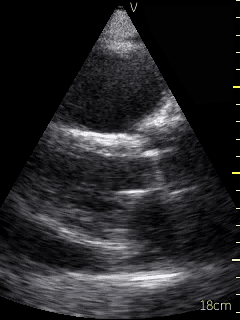

Video 1 (online supplement; Figure 1) demonstrates a parasternal long axis view with the pericardial effusion noted to be posterior to the left ventricle in this view. Video 2 (online supplement; Figure 2) is a short axis view of the heart which is showing that the effusion is surrounding the heart. Video 3 and 4 (online supplements; Figures 3 & 4) demonstrates that the pericardial effusion is present significantly surrounding the apex as well. An echocardiogram confirmed the POCUS findings and cardiology was consulted to conduct a pericardiocentesis, following which the patient’s symptoms resolved. The effusion was thought to be chronic and transudative. In this case, the use of POCUS at the bedside allowed for rapid detection of a large pericardial effusion and subsequent treatment.